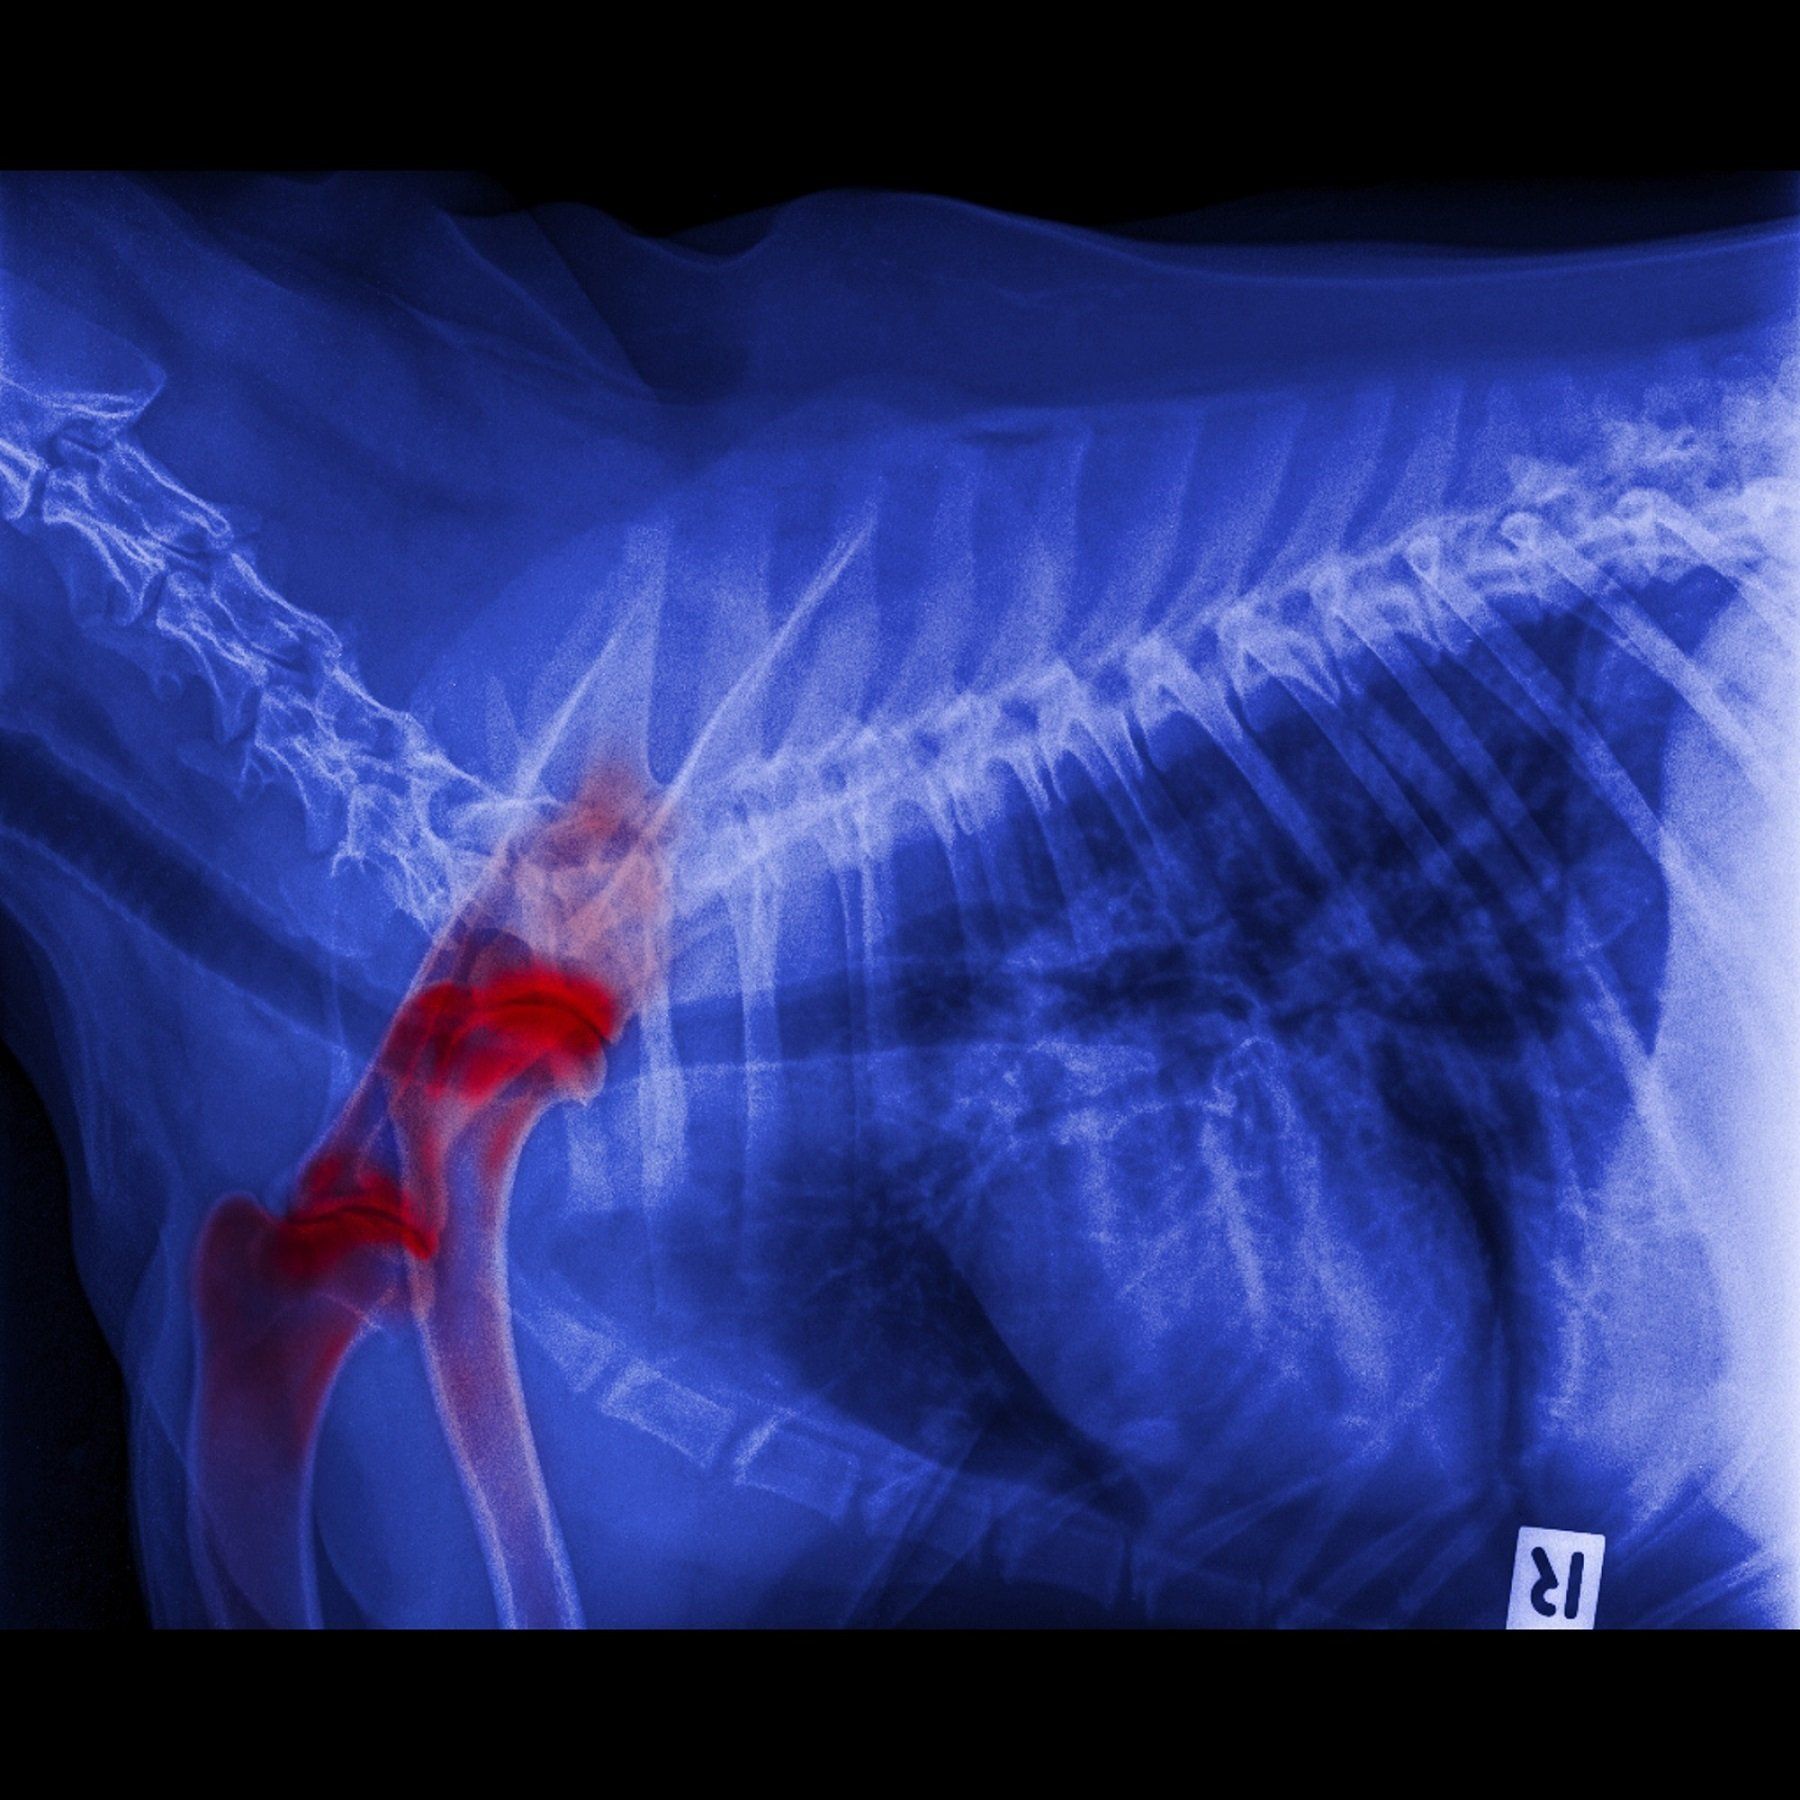

Radiologia clinica veterinaria

La radiografia è uno strumento importante che può aiutarci a fare una diagnosi corretta.

Una radiografia è un “tipo di fotografia” che può guardare all'interno del corpo e rivelare immagini che non possono essere, in alcun modo, rilevabili dall'esterno. La radiografia può essere utilizzata per valutare quasi ogni organo del corpo. Gli studi radiografici sono indispensabili nel primo approccio, soprattutto per le patologie dell’apparato locomotore.

La nostra clinica dispone di un apparecchio radiologico di ultima generazione ad alta frequenza con acquisizione digitale delle immagini radiografiche di alta definizione, che permette al medico di acquisire delle immagini in breve tempo. Grazie all'alta risoluzione delle radiografie, possiamo facilmente vedere organi in tutti gli animali, da uno più piccolo a uno grande. Possiamo valutare le diverse condizioni di salute, come ad esempio le masse tumorali, corpi estranei, le fratture delle ossa, patologie articolari, gravidanza e tutto quello che può essere rilevato con alta precisione e definizione dell'immagine.

Referente ufficiale della FSA: la clinica è autorizzata per eseguire gli studi radiografici della displasia dell’anca e del gomito, come struttura referente del territorio per conto della F.S.A. accreditata dall’E.N.C.I., per il controllo delle patologie ereditarie per la riproduzione selezionata di tutte le razze iscritte nel libro genealogico del E.N.C.I. (Disciplinare Ministeriale n. 20668 del 12.03.2002).